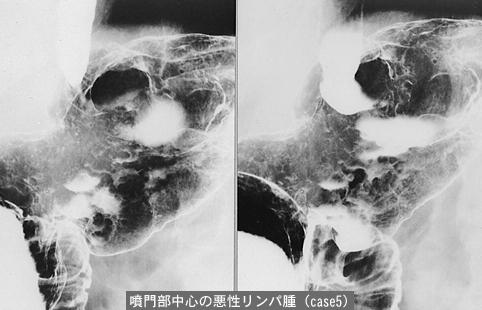

Various malignant tumors which developed at the boundary region of the digestive tract.

[ Image ID:11989 ]

Criteria of Hist.Classification

others/

Location

Stomach/More than one of above

Technique, Method

X-ray

Size